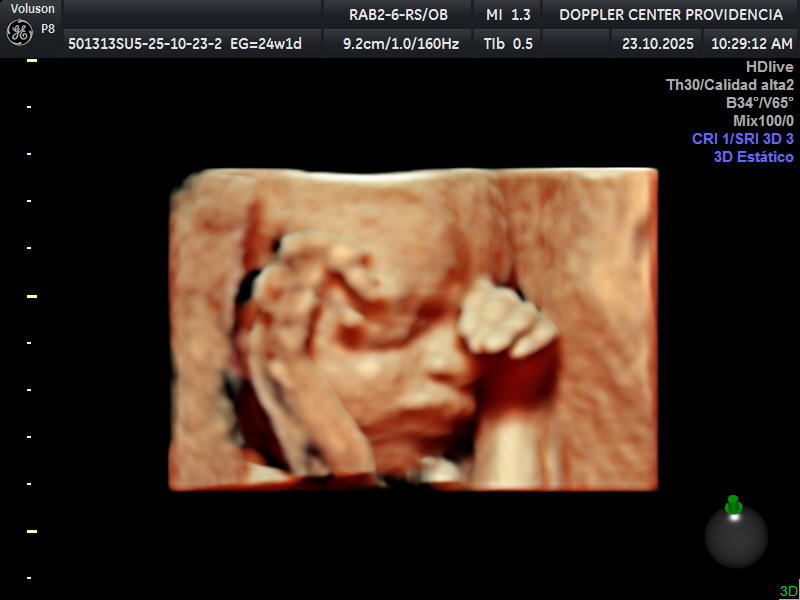

• Eco Doppler 22-24 semanas